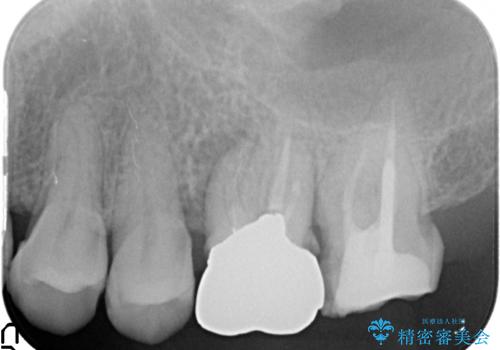

- 他院にて治療した左上奥歯の疼くような痛みが引かないため当院にいらっしゃった方の症例です。

検査の結果左上6に打診痛、根尖部圧痛、根尖病変を認めたため、再根管治療を行ったところ症状が緩解したため、オールセラミッククラウンによる補綴を行いました。

左上7は治療を希望されなかったため、オールセラミッククラウンによる補綴のみを行いました。